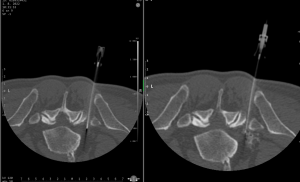

Průběh výkonu

- Výkon je obvykle rychlý a minimálně bolestivý.

- Pacient při výkone leží na břiše. Úvodem se provede vyšetření vybraného úseku páteře k přesnému zacílení výkonu. Po výběru místa vhodnému k vpichu je kůže zad natřena desinfekcí, případně je provedeno místní umrtvení kůže a podkoží zad Mesocainem.

- Poté je k nervovému kořeni zavedena velmi tenká jehla. Po přesném umístění hrotu jehly je k meziobratlovému otvoru aplikována směs 3,5 ml Marcainu a 1 ml Diprophosu.

Marcain je dlouhodobě působící lokální anestetikum. Diprophos kortikoid, který má protizánětlivé a antiedematozní účinky zmenšuje otok nervového kořene.

Co se vlastně při biopsii odehrává?

Na vyšetřovně, kde se bude výkon provádět je pacient uložen do polohy umožňující nejlepší přístup k ložisku. V této poloze musí po dobu výkonu pokud možno bez pohybu setrvat. Lékař provádějící výkon zaměří přístrojem ložisko, určí nejbezpečnější přístup, provede místní znecitlivění místa vpichu, zavede bioptickou jehlu, provede odběr vzorků. Poté jehlu odstraní a místo vpichu převáže.